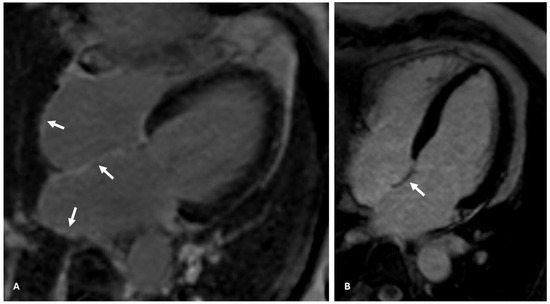

- McGann, C.; Akoum, N.; Patel, A.; Kholmovski, E.; Revelo, P.; Damal, K.; Wilson, B.; Cates, J.; Harrison, A.; Ranjan, R.; et al. Atrial fibrillation ablation outcome is predicted by left atrial remodeling on MRI. Circ. Arrhythmia Electrophysiol. 2014, 7, 23–30. [Google Scholar] [CrossRef]

- Kuppahally, S.S.; Akoum, N.; Badger, T.J.; Burgon, N.S.; Haslam, T.; Kholmovski, E.; Macleod, R.; McGann, C.; Marrouche, N.F. Echocardiographic left atrial reverse remodeling after catheter ablation of atrial fibrillation is predicted by preablation delayed enhancement of left atrium by magnetic resonance imaging. Am. Heart J. 2010, 160, 877–884. [Google Scholar] [CrossRef]

- Oakes, R.S.; Badger, T.J.; Kholmovski, E.G.; Akoum, N.; Burgon, N.S.; Fish, E.N.; Blauer, J.J.; Rao, S.N.; DiBella, E.V.; Segerson, N.M.; et al. Detection and quantification of left atrial structural remodeling with delayed-enhancement magnetic resonance imaging in patients with atrial fibrillation. Circulation 2009, 119, 1758–1767. [Google Scholar] [PubMed]